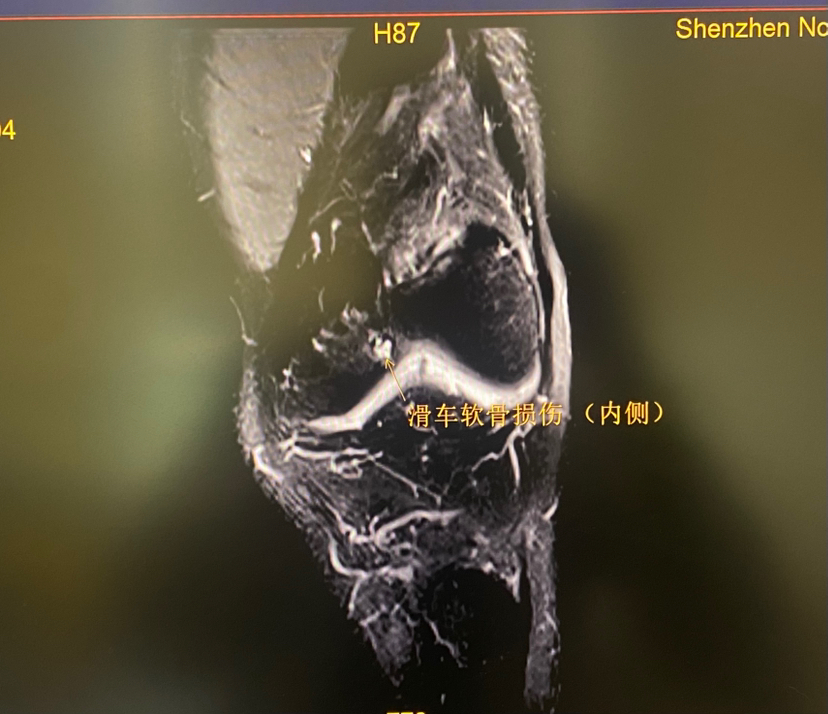

下面展示典型的膝关节软骨损伤,MRI核磁扫描可以清晰发现软骨损伤(3-4度),门诊检查非常常见!

滑车软骨损伤 (软骨剥脱,软骨下骨暴露)